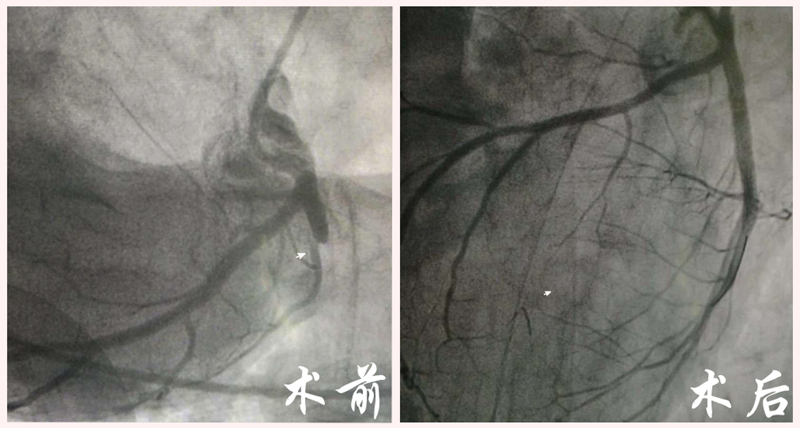

16:42 病人进入导管室。医生在DSA造影下发现他心脏左前降支第一对角支开口以远处完全闭塞,反复扩张球囊后,血流有恢复,但患者仍有明显胸痛症状,再次造影,发现前降支主干有头发丝粗细的残余血流。

使用导丝通过极其狭窄的病变处,再用球囊扩张血管、开通血流,并摆放支架,才解决了真正的“犯罪血管”。患者胸痛症状也得到了明显的改善。